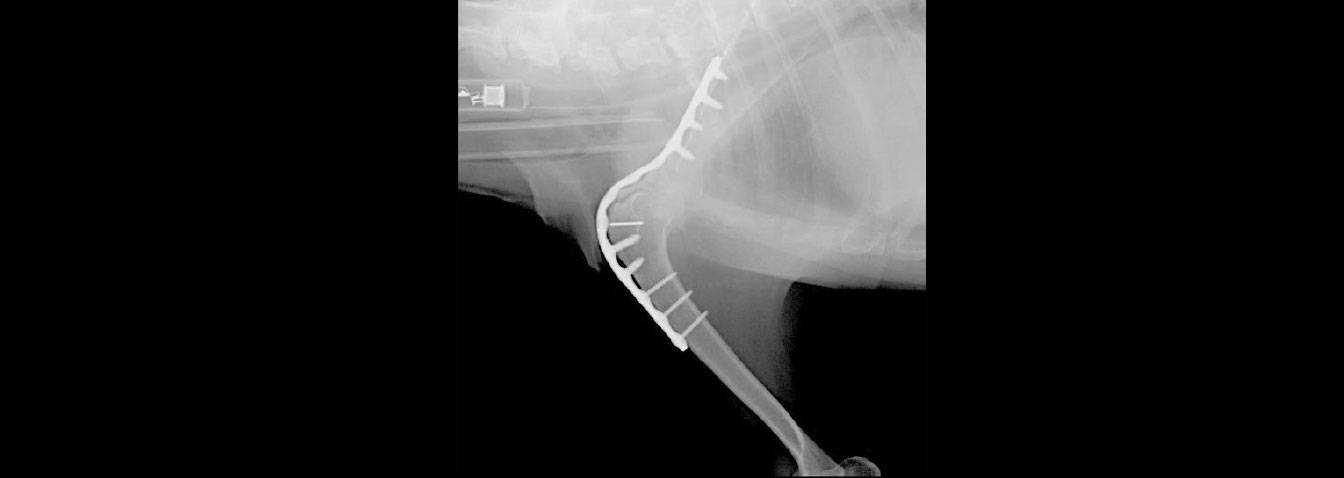

当院ではKYON社のALPS®︎(チタンプレートとチタンスクリュー)を使用した肩関節固定術を行っております。

犬の肩関節固定術では、関節軟骨の除去を確実に行うために、肩甲骨(関節窩)と上腕骨(骨頭)の両方の表面を外科的に削り、骨同士が直接接触する状態にします。

手術後